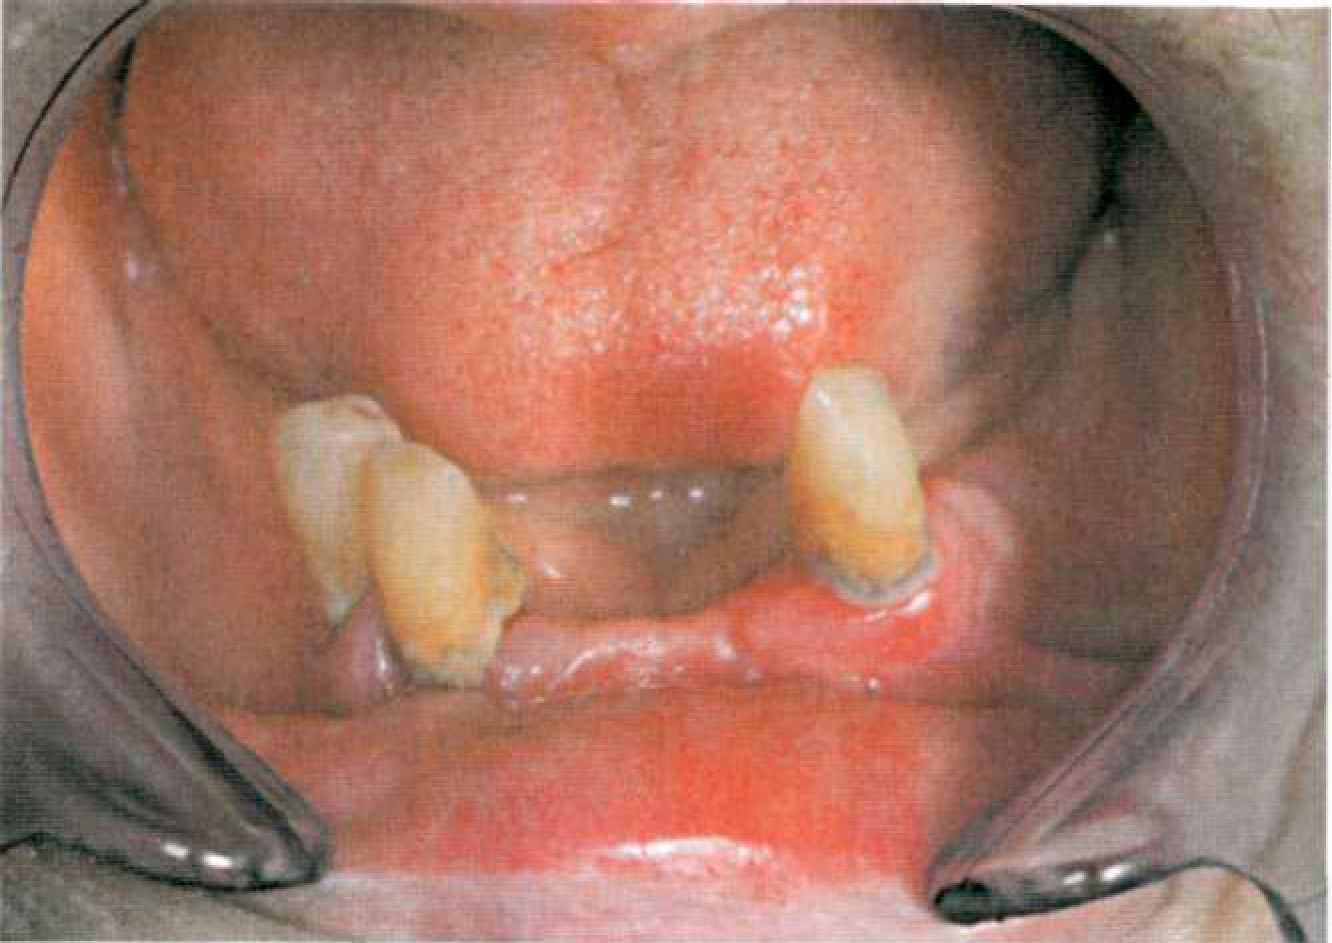

Рис.91. Препарирование при применении интракоронарных замковых креплений Препарирование при применении телескопических фиксаторов Препарирование опорных зубов при применении телескопических фиксаторов проводят с круговым поддесневым уступом в 135° и сохранением высоты коронковой части не менее 5 мм (рис. 92). По сравнению с препарированием под металлокерамическую коронку сошлифовывается на 0,3 мм больше твердых тканей для размещения первичной коронки. В работе можно использовать алмазные турбинные боры: № 314.697.524 для маркировки кругового уступа, для снятия слоя эмали № 314.142.534, для препарирования дентина № 314.173.524; № 314.131.514 для предварительного оформления уступа № 314.033.534 для обработки окклюзионной поверхности (формы рабочей части даны по стандарту ISO). Окончательное оформление уступа проводится микромотором со скоростью вращения до 50 тыс. об./мин алмазными или твердосплавными борами. Препарированиезавершается сглаживанием острых кромок и маркировкой вертикагьного желобка по месту изготовления фрикционного штифта. Рис.92. Препарирование опорных зубов под телескопическую коронку При незначкельном количестве сохранившихся зубов, когда и применяются главным образом телескопические коронки, на опорных зубах оченьчасто определяется пародонтальный карман, глубиной более 1,5 мл. При нормальных условиях граница препарирования лежит у дна зубодесневой борозды, здесь проходит замыкающий край телескопичэской коронки. В условия пародонтального кармана не следует стремиться проводить препарирование на всю глубину. Чем глубже в пощесневую область планируется погружение края коронки, тем больие неточностей может возникнуть при снятии оттисков и, в конечном итоге, ухудшится качество прилегания первичной коронки к отпрепарированному зубу, что может приводить к хронической травме дэсневого края, ретракции десны и развитию вторичного кариеса под коронкой. Поэтому целесообразно в условиях пародонтального кармана проводить поддесневое препарирование на глубину не более 1 мм или проводить предварительную пародонтологическую коррекцию хирургическим способом. Поддеснева! часть отпрепарированной культи закрывается только каркасом перзичной коронки, поэтому поддесневой край внутреннего телескопа специально выделяют путем полировки от поверхности сцеплени!, покрываемой наружным телескопом. Край наружюй телескопической коронки заканчивается непосредственно перед десневым краем и не погружается под десну. Слишком длинный наружный телескоп, который погружается в поддесневую область вызывает образование неприятного запаха вследствие того, что в «зазор» между первичной и вторичной коронками всасывается жидкость из зубодесневой борозды. Поэтому внутренняя телескопическая коронка длиннее наружной коронки на величину поддесневого полированного края (рис. 93).

| КЛИНИКО-ЛАБОРАТОРНЫЕ ЭТАПЫ ИЗГОТОВЛЕНИЯ КОМБИНИРОВАННЫХ ПРОТЕЗОВ С ЗАМКОВОЙ И ТЕЛЕСКОПИЧЕСКОЙ ФИКСАЦИЕЙ ПРЕПАРИРОВАНИЕ ОПОРНЫХ ЗУБОВ Одним из наиболее важных факторов, определяющих успех лечения, является правильное препарирование опорных зубов. При протезировании комбинированными протезами существует несколько видов подготовки твердых тканей опорных зубов: • при применении замковых креплений; • при применении телескопических коронок; • при применении покрывных протезов. Препарирование при применении замковых креплений Препарирование опорных зубов при применении полулабильных и лабильных экстракоронарных замковых креплений ничем не отличается от препарирования под металлокерамическую коронку. Следует соблюдать следующие правила: высота культи должна быть не менее 5 мм, конусность стенок 2-3°. На фронтальных зубах создается прямой или 135° вестибулярный уступ и символ уступа с оральной поверхности. На жевательных зубах — круговой уступ в 135°. При препарировании для применения жестких экстракоронарных аттачменов с обязательным фрезерованием опорных коронок следует подготовить достаточно места для размещения интерлоков в межзубных промежутках и фрезерованных ответвлений съемной части протеза с оральной поверхности, чтобы избежать увеличения контура опорных коронок. Оптимальная толщина фрезерованного ответвления и диаметр интерлока составляют 0,8 мм. Поэтому с оральной поверхности следует создать уступ шириной 1,1 мм, а в межзубном пространстве расстояние между проксимальными стенками опорных зубов должно составлять не менее 1,4 мм. Положение уступа по отношению к десневому краю (наддесневое, придесневое и поддесневое) определяется эстетическими условиями и кариозным разрушением твердых тканей (рис. 89).